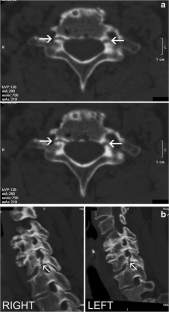

Atypical, unusual, and misleading imaging presentations of spondylolysis

Although lumbar spondylolysis is a widely known and easily recognizable condition in its typical presentation, there are some less well-known forms that may occasionally be challenging and/or demand special attention on imaging. Examples include: acute and/or incomplete lesions; unilateral defects; lesions at unusual levels (cervical, upper lumbar, and multi-level spondylolyses); iatrogenic lesions; non-isthmic spondylolysis; and spondylolysis related to underlying diseases. In addition to their atypical, uncommon or confusing imaging presentations, these forms of spondylolysis are far rarer than the classic type and have been described, to a great extent, in the surgical literature, thus reducing the awareness of radiologists about them and raising the potential for misdiagnosis and inadequate treatment. In this review the authors address these special manifestations of spondylolysis, stressing the more important features to be considered in the differential diagnosis and the impact of a precise diagnosis of spondylolysis on the patient’s care.